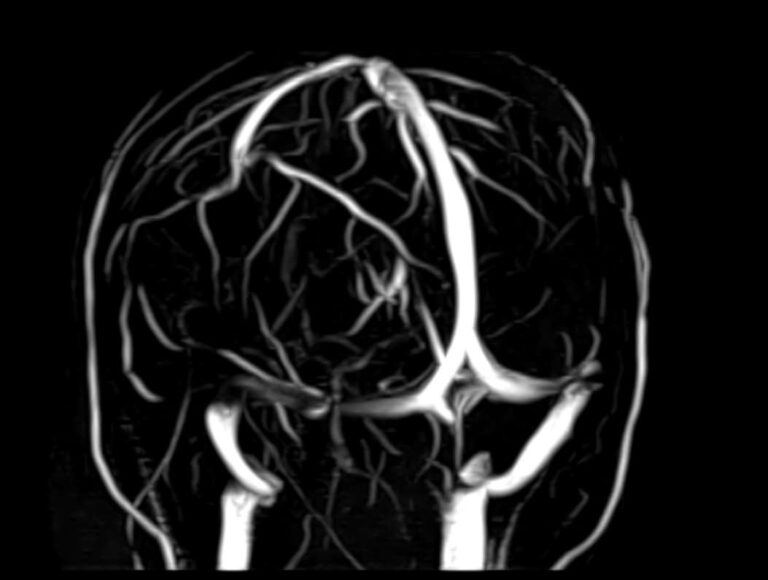

Исследования выполняются на современном высокопольном томографе экспертного класса TOSHIBA VANTAGE TITAN 1,5 Тесла, который использует разные режимы сканирования с толщиной среза от 1мм в различных плоскостях с последующей цифровой обработкой полученных данных для создания трехмерных изображений. МР-ангиография отображает состояние артериальной системы кровоснабжения головного мозга. МР-венография головного мозга позволяет детально изучить особенности венозного русла головного мозга.

Компьютерная программа обрабатывает данные, полученные при сканировании, и формирует объемные изображения как самого мозга, так и сосудистой системы в отдельности без прилегающих тканей. Методики применяются одновременно и взаимодополняют друг друга.